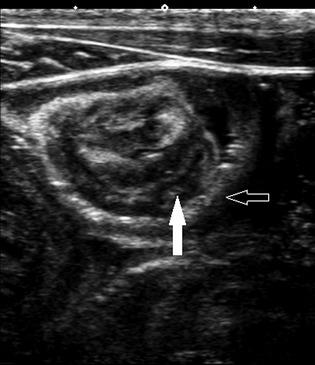

The reference ranges (95% predictive interval) for wall thickness were 1.6-3.6 mm for the stomach, 1.9-3.2 mm for the duodenum, 1.9-3.1 mm for the jejunum, 1.3-2.2 mm for the colon, and 0.8-2.7 mm for the cecum. Intraobserver wall thickness CV ranged from 8 to 21% for the 2 observers for 5 gastrointestinal segments. The interobserver bias for wall thickness measurements was not significant except for the stomach (0.14 mm, P < .05) and duodenum (0.29 mm, P < .05). Diagnostic images of mural blood flow could not be obtained. Asymptomatic intussusceptions were found in 10/18 neonates. Associations between sonographic variables or age and the presence of intussusceptions were not found.

Sonographic characteristics of the GI tract of normal Standardbred neonates can be useful in evaluating ill foals. Asymptomatic small intestinal intussusceptions occur in normal Standardbred neonates.

正常标准赛马新生幼驹胃肠道的超声特征有助于评估患病幼驹。正常标准赛马新生幼驹会发生无症状小肠肠套叠。